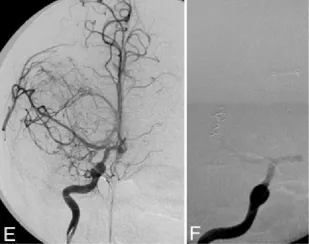

E:右侧颈内动脉注射的右前斜位造影图像,显示大脑中动脉远端M1和M2分支变细,并可见肿瘤性毛细血管染色。F:右侧颈内动脉注射早期动脉期获取的斜位图像,显示弹簧圈从大脑中动脉三分叉动脉瘤部位挤出。